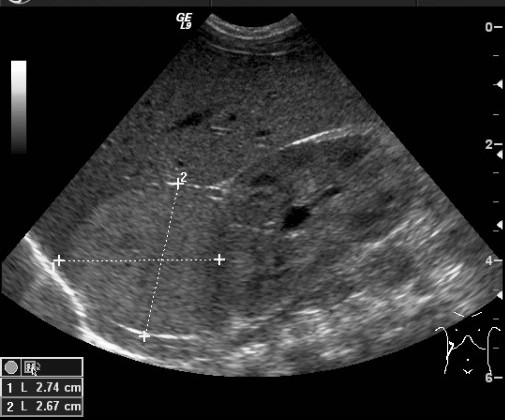

25. US examination, longitudinal view. Above the right kidney, in the adrenal region a solid, slightly inhomogeneous mass can be seen. Neuroblastoma.

27. A solid, echogenic mass arising from the right kidney. Wilms tumor. Abdominal US.